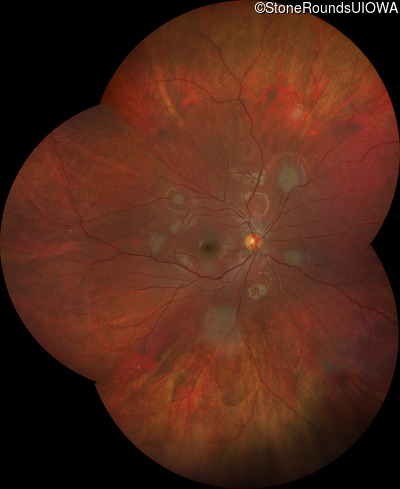

Fundus Montage - Right - 20/25 +2 sc

Exemplar